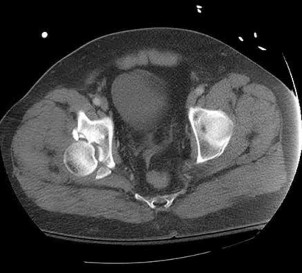

The injury pattern shown in the CT image in Figure 26 is most commonly associated with which mechanism?

Posterior shoulder dislocations are most commonly the result of seizures and electrical shock. Collision athletic events, postpolio syndrome, and traction injury are rarely associated with posterior shoulder dislocations. The bony defect caused by impaction of the anterior superior humeral head on the posterior glenoid has been referred to as a “reverse Hill-Sachs lesion.”